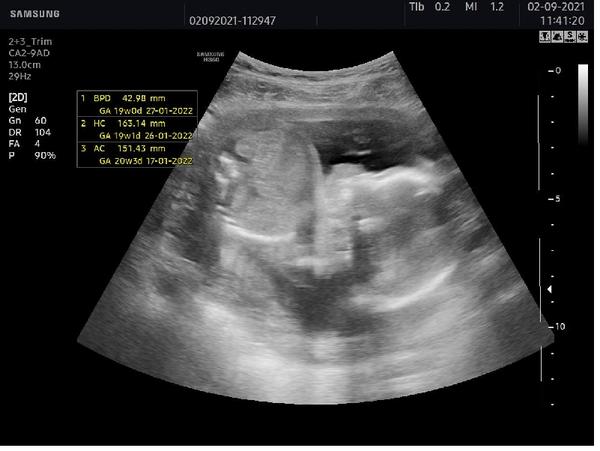

Dobrý den jsem dnes 19+3tt, včera jsem byla na prohlídce u svého dr. Který mi sdělil pohlaví miminka ale tak trošku nejistě. Prý vypadá to na holku myslíte že mám naději ještě že by se z toho mohl vyklubat chlapeček. Podotýkám že nás bývalý pan dr. Náš posílal na velký utz na fifejdy ke specialistovi. Ale můj nový dr. To dělá sám a utz nemá moc kvalitní, přikládám foto. Stalo se vám některé ze by v pozdějším stádiu těhotenství změnil názor na pohlaví? Předem děkuji za odpovědi

@sherryel vám to jde krásně vidět jenže mne doktor řekl na minulé kontrole že mne bude vyšetřovat 25min no a včera když sem tam přišla byla jsem objednaná na 10:15 vzal mne až za hodinu a utz tvrval že vsim všudy asi 10min a ještě k tomu sem tlna tom utz nic nevidela jak to rychle prejizdel poznala jsem jen srdíčko a ruce nevím zda tomu věřit mám foto s třetího měsíce a tam mi přijde že tam ten pinda je no je pravda že v těch utz se moc dobře nevyznám. Co myslíte?

@andysek1235 objednala bych se na 2. screening na genetiku, moc bych tomuto utz nevěřila (pohlaví je to nejmenší). Byla jsem na genetice i u svého dr a je to nesrovnatelné, a to můj doktor nemá špatný přístroj. Ale na genetice vyšetření trvalo skoro půl hodiny, vše opravdu pečlivě, u mého tak 5 minut (a o genetice nevěděl).

@andysek1235 : u nás jsou tam viditelné dva ovalky a je to na 90% holka. U kluka byl ult. Hodně průkazný ( úplný pornoherec ) ...